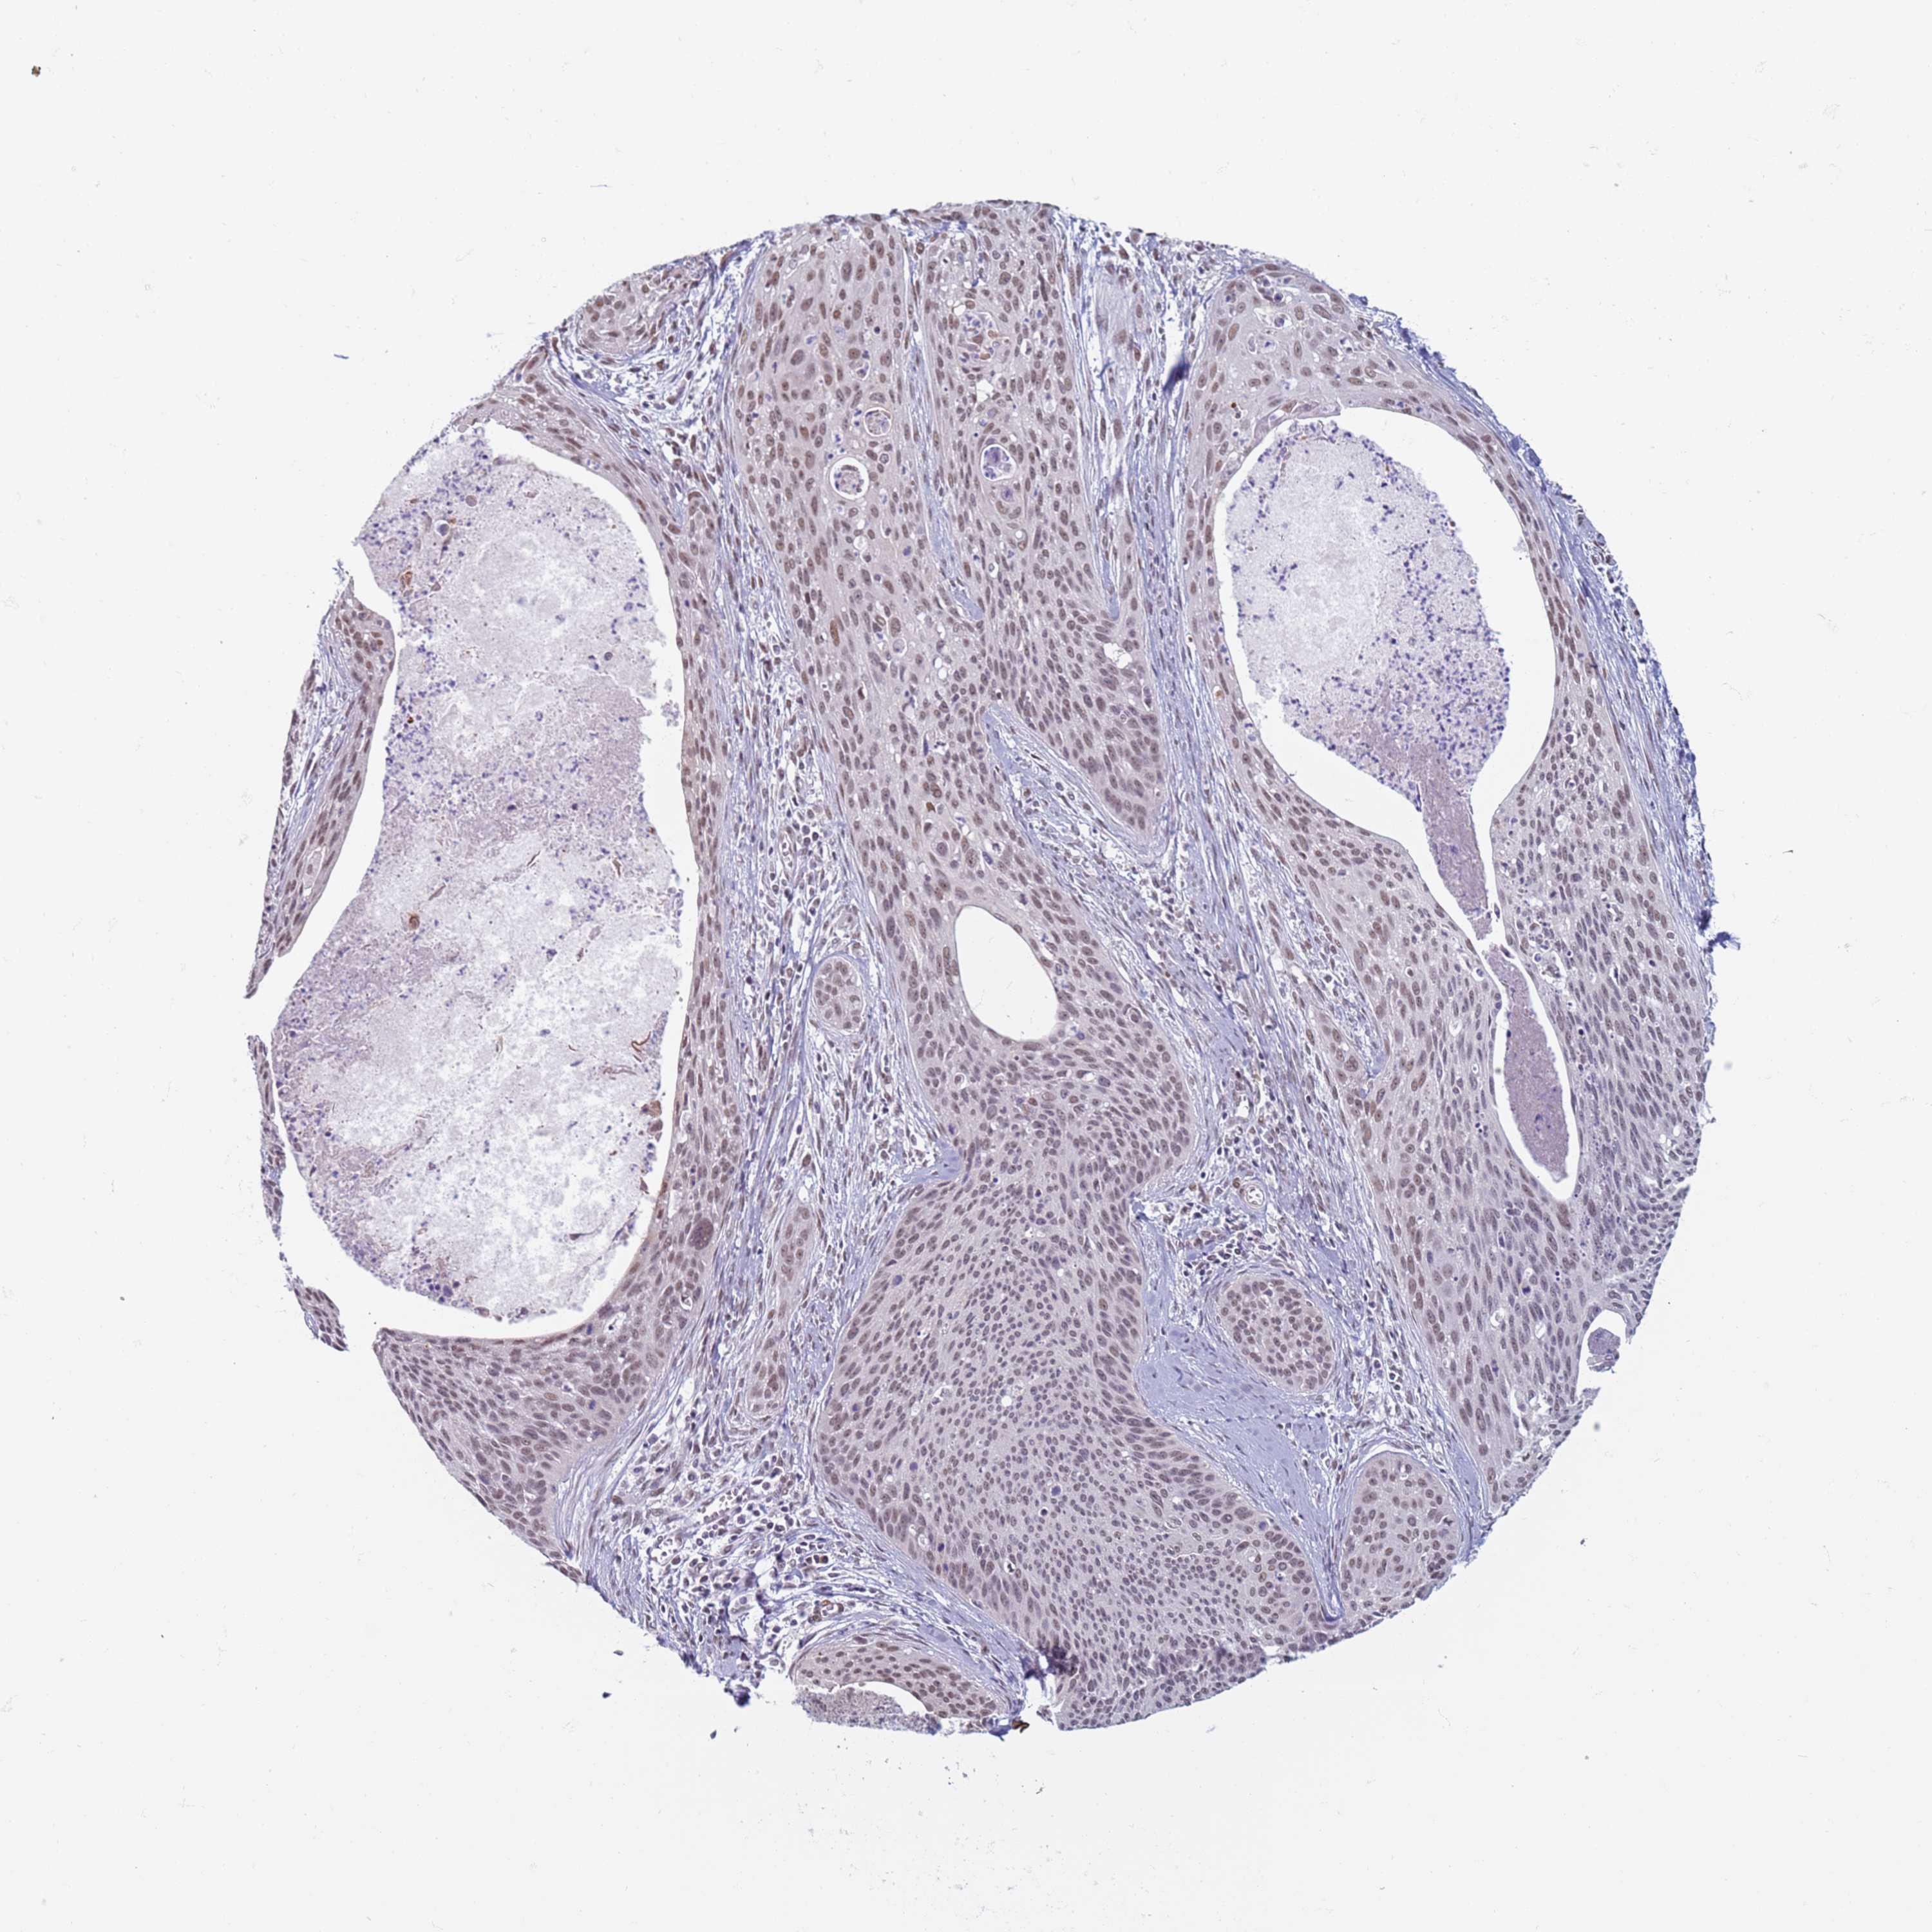

CERVICAL CANCER - Protein expressioni

A mouse-over function shows sample information and annotation data. Click on an image to view it in a full screen mode. Samples can be filtered based on level of antibody staining by selecting one or several of the following categories: high, medium, low and not detected. The assay and annotation is described here.

Note that samples used for immunohistochemistry by the Human Protein Atlas do not correspond to samples in the TCGA dataset.

Antibody stainingi

Antibody staining in the annotated cell types in the current human tissue is reported as not detected, low, medium, or high, based on conventional immunohistochemistry profiling in selected tissues. This score is based on the combination of the staining intensity and fraction of stained cells.

Each image is clickable and will lead to virtual microscopy that enables deeper exploration of all samples and also displays staining intensity scores, fraction scores and subcellular localization as well as patient and tissue information for each sample.

Antibody HPA041906

Antibody HPA043552

Staining

High

Medium

Low

Not detected

Intensity

Strong

Moderate

Weak

Negative

Quantity

>75%

75%-25%

<25%

None

Location

Nuclear

Cytoplasmic/membranous

Cytoplasmic/membranous,nuclear

Squamous cell carcinoma, NOS

Adenocarcinoma, NOS